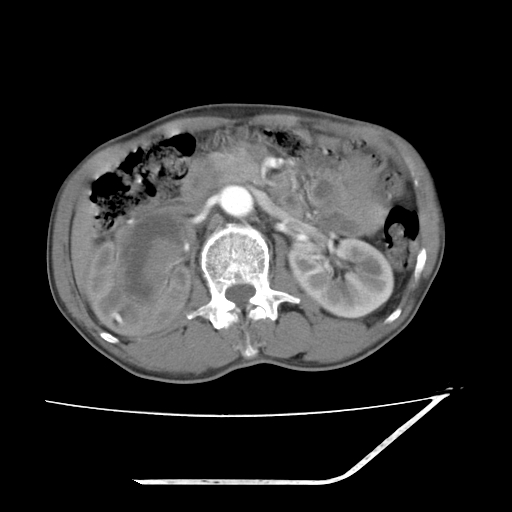

平扫

考虑右肾盂癌,肾动脉受侵,右肾功能减退,右肾盂输尿管积水,管壁增厚,考虑种植转移,应该把下面扫完的

支持右侧肾盂癌伴肾静脉瘤栓形成可能性大,右肾结石.肝右叶后段低密度影,不除外转移.

右肾盂旁ca并肾静脉瘤栓形成/肾功能降低。

右肾结石。

右肾盂癌,肾动脉受侵,右肾盂输尿管积水,管壁增厚,考虑种植转移

支持 右侧肾盂癌伴肾静脉瘤栓形成可能性大,右肾结石;肝右叶后段低密度影,不除外转移。

1.右侧肾盂癌伴肾盂积水。

2.肾脏功能减退,原因有:(1)肾动脉受侵。(2)肾静脉受侵(3)肾积水,等。本例,肾动脉显影较好,但受压明显;肾静脉无明显显示,受压或静脉癌栓,下腔静脉腔内未见明显充盈缺损。

3.右侧上段输尿管扩张,原因:(1)积水所致;(2)种植。